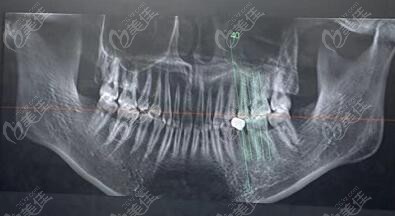

种牙擅长:ALL-ON-4半口种植技术

医生特色简介:汪龙河在牙齿种植、全口牙齿修复及牙周病的治疗方面积累了丰自富的临床经验。

▼顾客多颗牙松动,找汪龙河医生做的all-on-6全口种植病例▼

2025合肥种植牙医生推荐:汪龙河